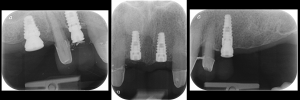

Five implant fixtures were placed using a fully guided surgical protocol. Fig. 6

Periapical radiographs to verify the seat of the digital scan bodies. Fig. 12

Periapical radiographs to verify the seat of the implant- retained provisional restorations. Fig. 18